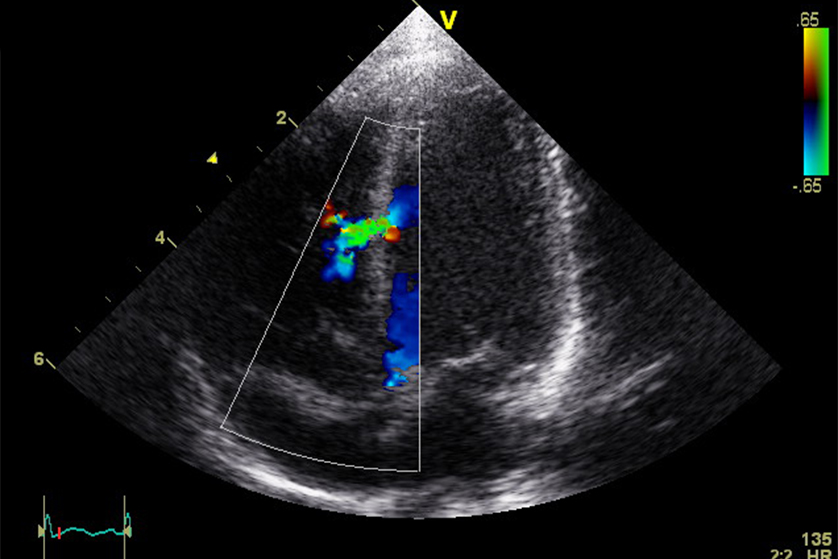

ekokardiyografi

Ekokardiyogram ultrason dalgaları ve bir bilgisayar kullanılarak çalışan kalbin...

Detaylı Bilgi >